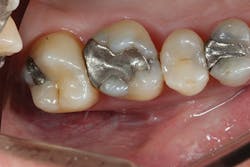

Before I began prepping for the crown, I used CariVu. On the images, I saw not only a crack on the tooth that was to be crowned, but also clear caries on the adjacent tooth (figure 6). During treatment, I snapped a picture of the preparation on tooth No. 2 with an SLR extraoral camera (figure 7). I took an additional photo midtreatment to show how far the cavity had progressed into the dentin. The bitewing didn't show any of this decay. This caries detection technology gives me a great opportunity to tell patients that I found a cavity that we would not have known about until it caused trouble. There is no surprise later and no apologies for missing an early lesion.

Figure 7: Open tooth image for No. 2, confirming mesial caries.